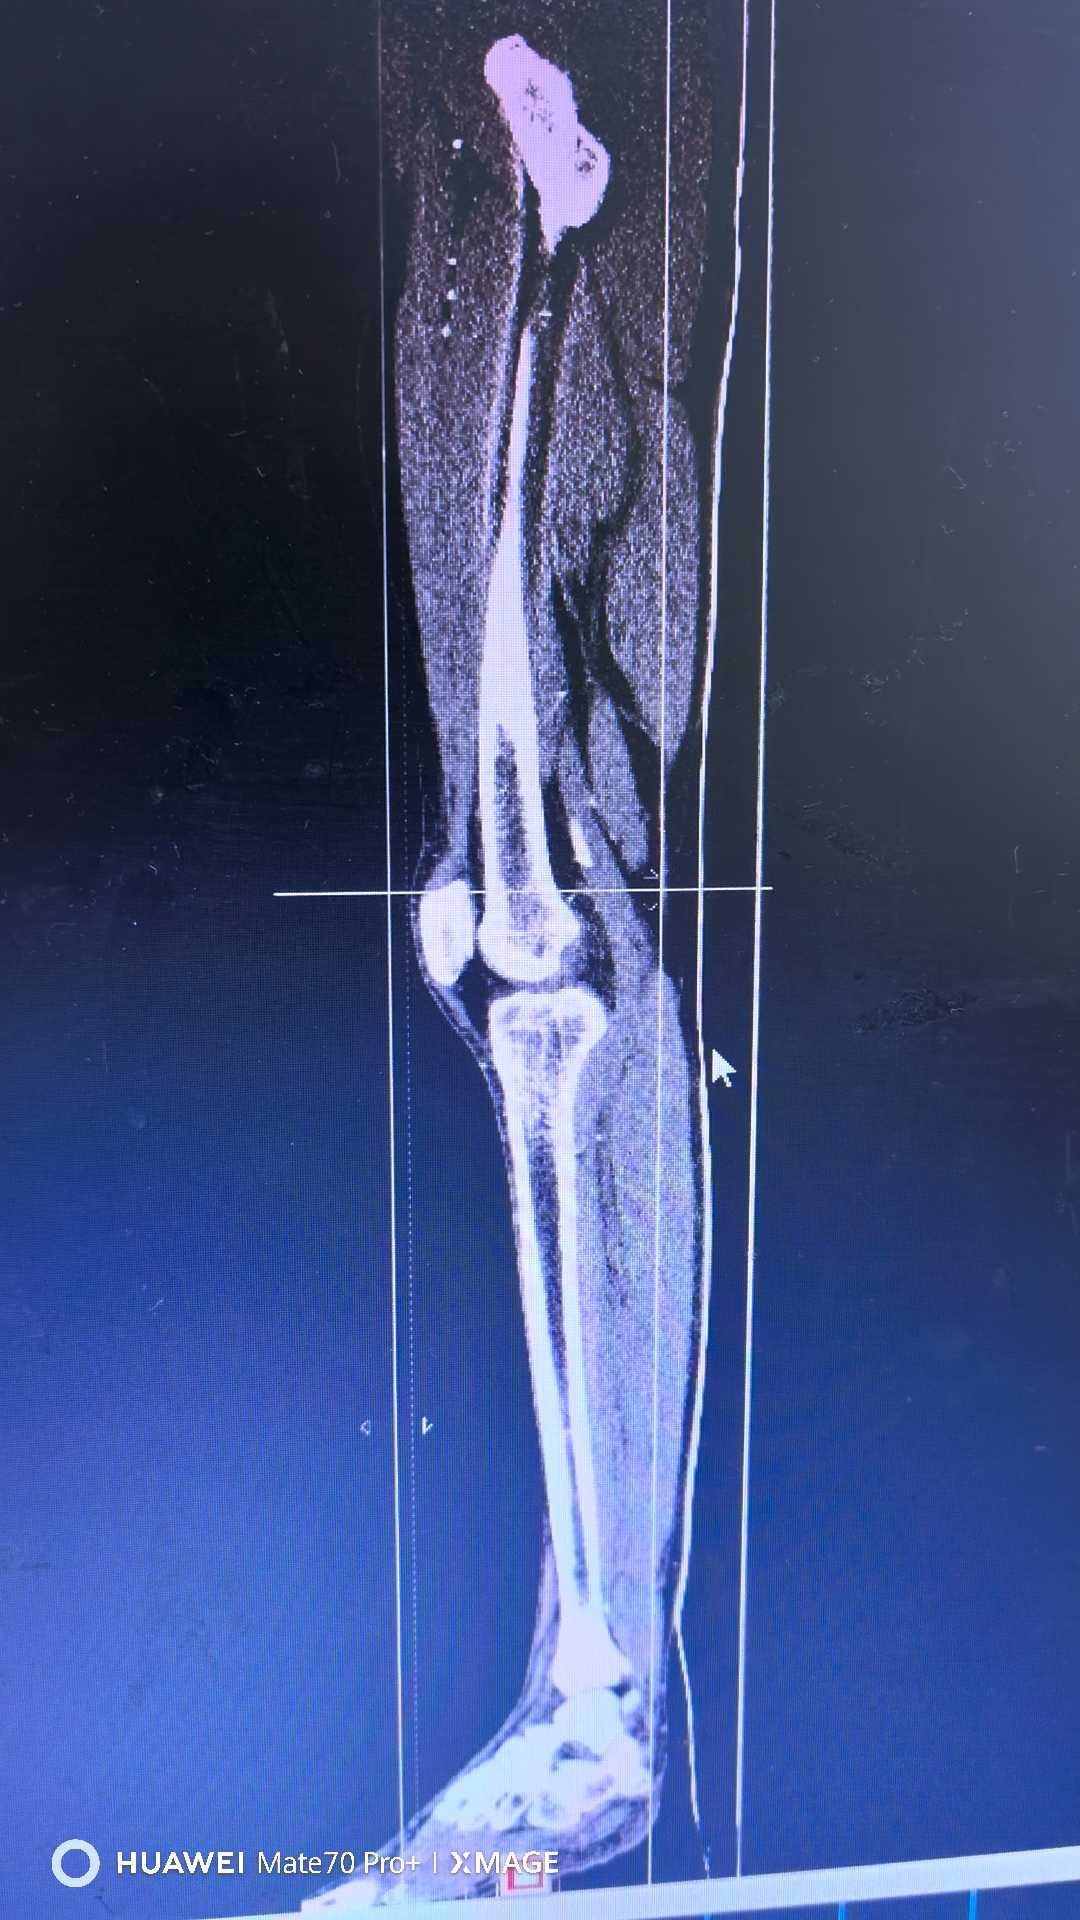

【检查】:

【临床诊断】:右下肢动脉闭塞(腘窝段)